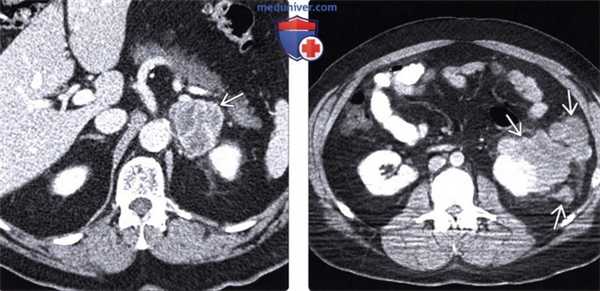

(Слева) При аксиальной КТ с контрастным усилением определяется объемное образование, интенсивно накапливающее контраст, неоднородной, дольчатой структуры в левом надпочечнике у пациента с меланомой, пролеченного десять лет назад. Путем биопсии было установлено, что данное образование является метастатической меланомой.

(Справа) При аксиальной КТ с контрастом выявлено несколько отдельно лежащих объемных образований неоднородной, дольчатой структуры, расположенных в околопочечных тканях у пациента с меланомой. Метастазы меланомы имеют уникальную предрасположенность к поражению околопочечных тканей.